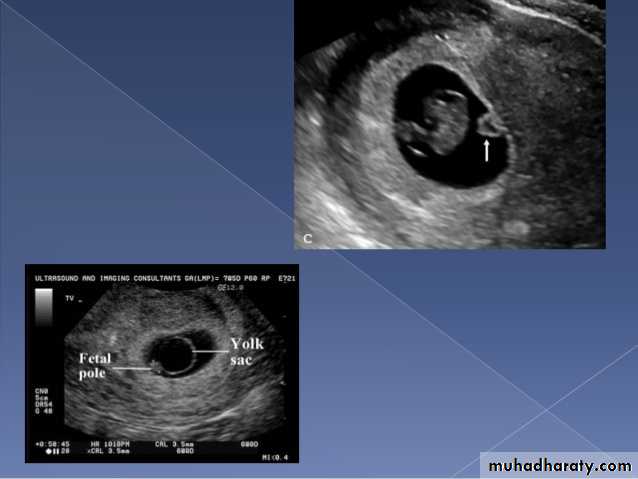

An anembryonic pregnancy may be diagnosed when there is no fetal pole identified on endovaginal scanning , and:

the size of the gestational sac is such that a fetal pole should be seen: MSD ≥25 mm on TVS (by RCOG criteria)